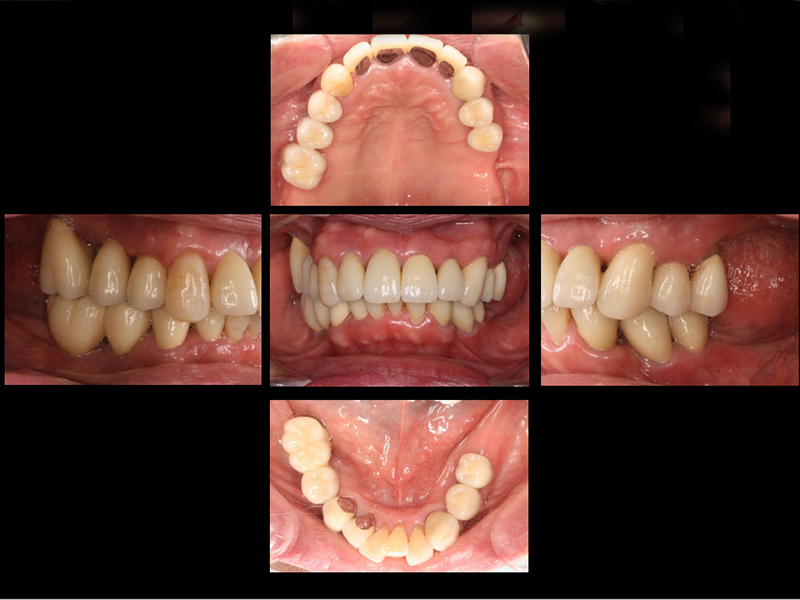

初診時口腔内写真